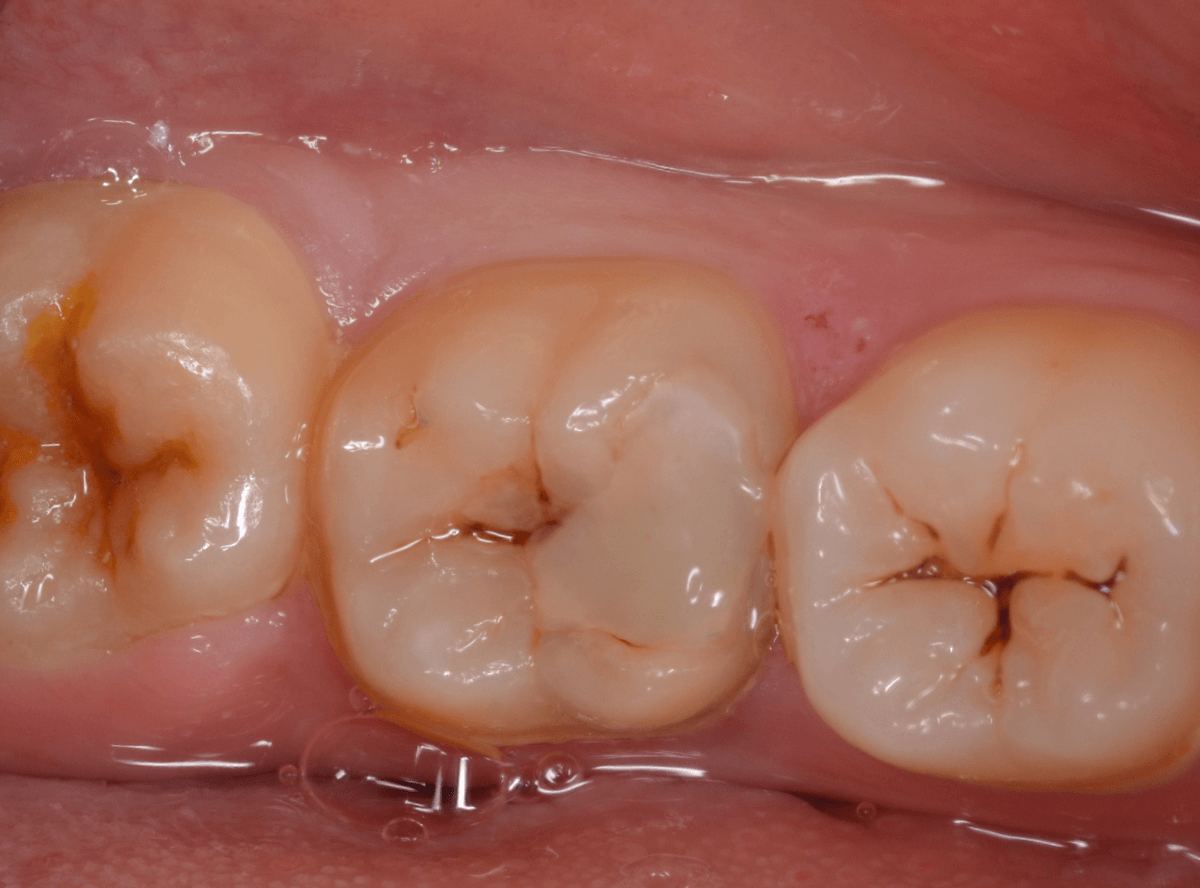

Case.13 問題なさそうなレジンの下で深い虫歯

他の歯の治療希望で来院された患者さんで、レントゲンで大きな虫歯が見つかった方です。

以前に虫歯を削って、レジンをつめる治療がしてあります。

表面を見る限り、特に問題はなさそうです。

レントゲン写真を撮影しました。

青い線が神経

黄色い線がレジン

赤い線が虫歯

です。

思ったよりも深い虫歯をレジンで埋めてあったようで、さらにその中が虫歯になっている状況です。

神経までかなり近い虫歯と思われます。

症状はありません。